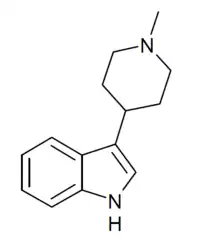

Related compounds

A number of related compounds are known, with a similar structure but having the indole core flipped and/or replaced with related cores such as indoline, indazole, benzothiophene, or benzofuran. These similarly are primarily active as agonists at the 5-HT2 family of serotonin receptors, with applications in the treatment of glaucoma, cluster headaches or as anorectics.

SN-22 | 3-(1-methylpiperidin-4-yl)-1H-indole | 17403-07-5 |